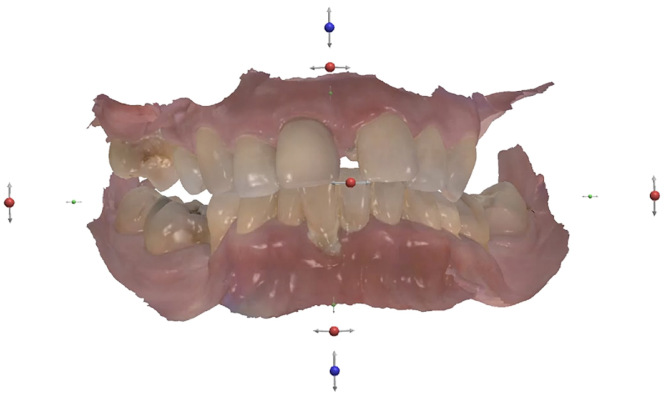

Fig. 2

No abnormalities were found during the extra-oral examination. The patient presented with a low smile line. The intra-oral examination revealed terminal dentition due to generalised periodontal disease. The patient presented with severe resorption of the posterior maxilla bilaterally (Fig. 1). The radiographic examination showed generalised alveolar bone resorption with vertical bone defects (Fig. 2).

In accordance with the radiographic and clinical evaluation, the patient case was classified as surgically and prosthodontically complex in terms of the International Team for Implantology’s SAC classification (Fig. 3). The SAC classification aids in assessing the degree of difficulty and risk associated with implant-related rehabilitation.